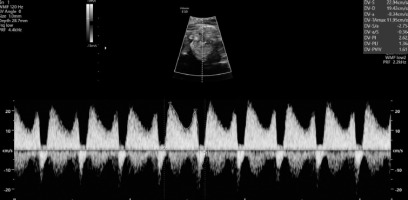

The swelling of the entire fetus was visualized – NT 5 mm (Figure 6) and reverse flow in the ductus venosus (Figure 7).